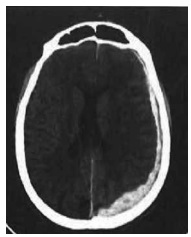

Considere-se esta imagem de uma lesão cerebral.

Com base nessa imagem, assinale a alternativa correta.